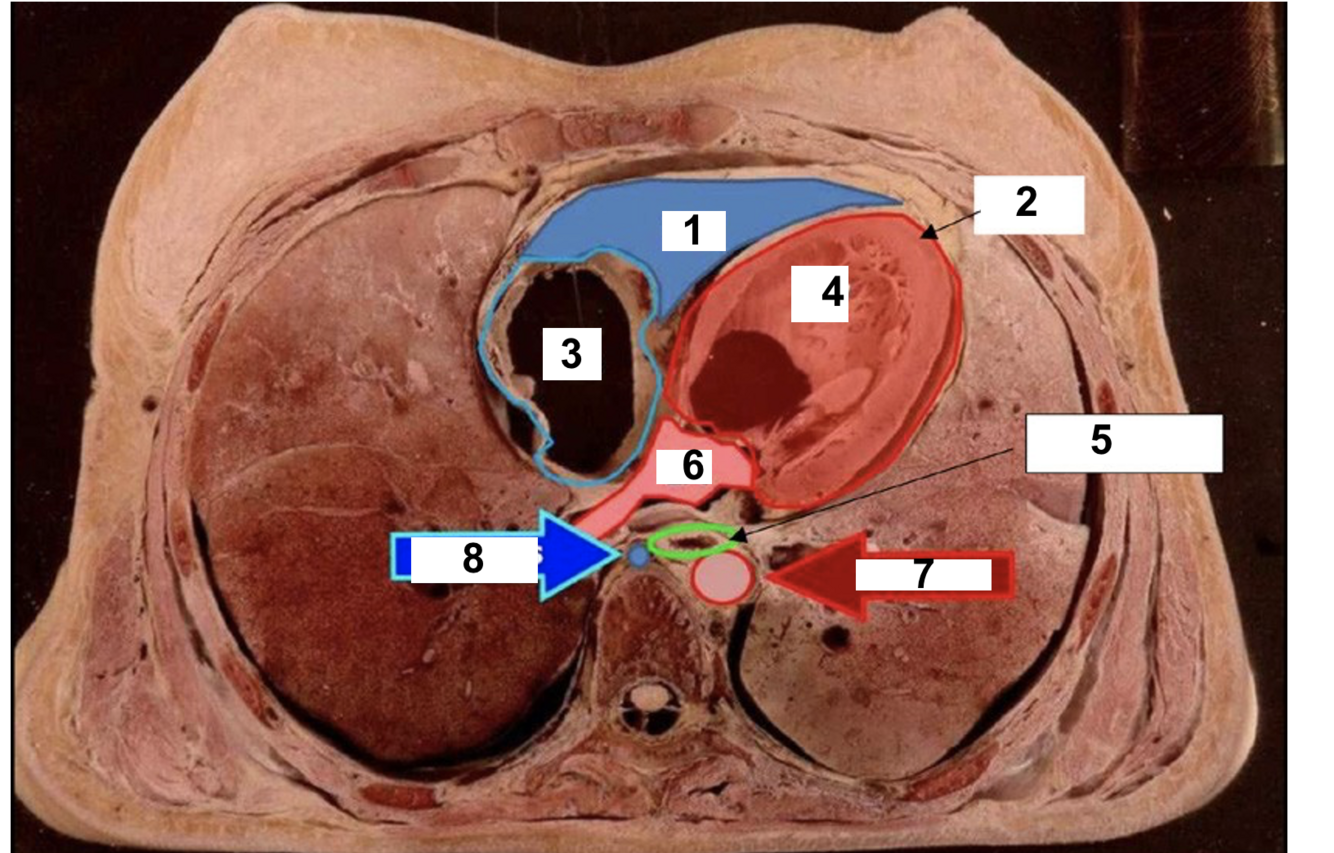

14

label 1

RV

15

2

Apex

16

3

RA

17

4

LV

18

5

oesophagus

19

6

LA

20

7

aorta

21

8

azygos vein